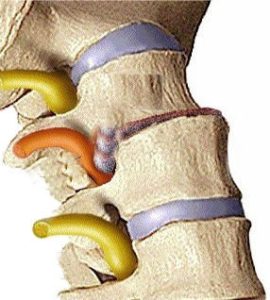

To częsty błąd. Dysk nie jest kością, lecz elastycznym „poduszkowym” tworem zbudowanym z dwóch elementów:

Jądra miażdżystego – galaretowatej substancji w centrum, która rozkłada siły nacisku i działa jak amortyzator.

Pierścieni włóknistych – mocnych, kolagenowych warstw otaczających jądro i utrzymujących jego kształt.

Dzięki tej budowie dysk może się odkształcać pod obciążeniem, ale nie traci przy tym objętości — to sekret jego sprężystości i zdolności do amortyzacji ruchu.

„Wypadnięcie dysku” to w rzeczywistości przepuklina krążka międzykręgowego, czyli pęknięcie pierścienia włóknistego i przemieszczenie części jądra miażdżystego.

Można to przyrównać do ściśnięcia gąbki z wodą – przy zbyt dużym nacisku część płynu wydostaje się na zewnątrz. Sama gąbka jednak zostaje tam, gdzie była.

Dysk także nie „wypada”, tylko jego zawartość może przemieścić się w stronę nerwu.